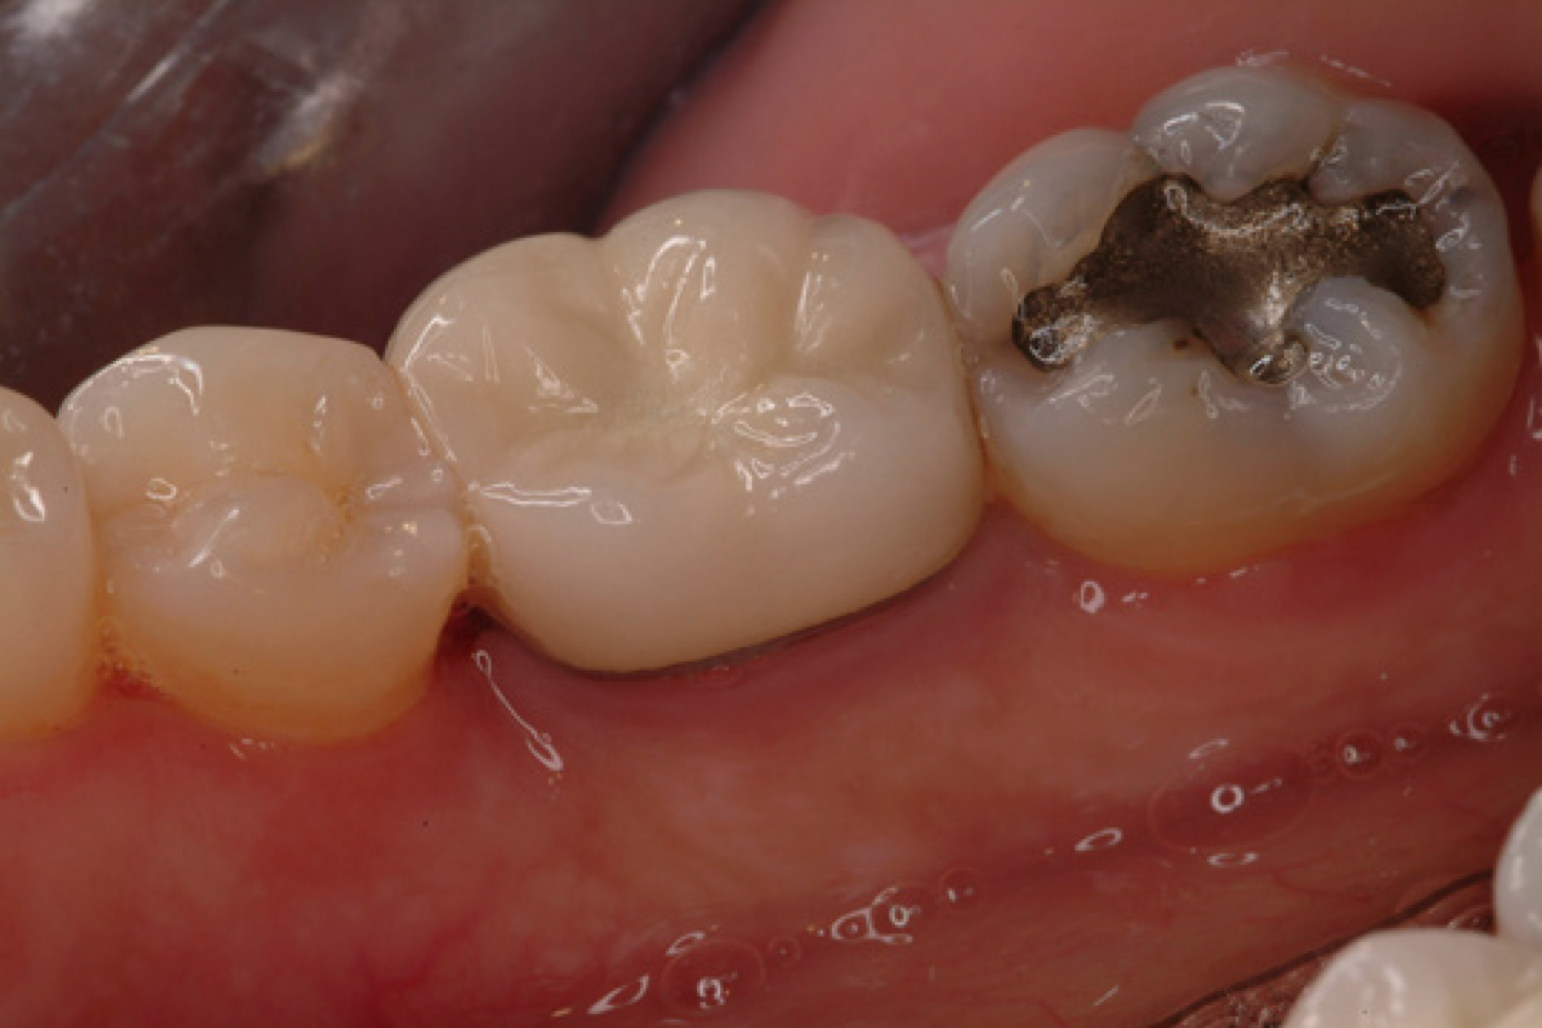

Amalgam materials – The first reported use of amalgam as a restorative material dates back to 659 AD in China. Amalgam is a substance that combines two or more different metals, usually silver, copper, zinc, and tin to form an alloy. This alloy is combined with mercury to make dental amalgam. Various groups have tried to have amalgam banned because of the toxicity of mercury in certain situations. Studies continue to show amalgam as a safe, affordable, durable, restorative material, backed by the American Dental Association and governmental agencies. Amalgam is still a common material used for dental restorations today (Figure 1).

Advantages of amalgam include its durability and long lasting restorations, ease of use in hard to reach areas, or in areas where isolation of fluids is a problem. It is time efficient, which is important when children are uncooperative. Disadvantages of amalgam include its color, concerns about mercury content, and the possible need for the removal of healthy tooth structure for mechanical retention. (For more information on mercury refer to the ADAA course Mercury in Dentistry - The Facts.)